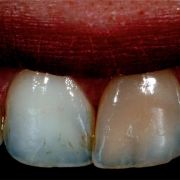

The tooth is discolored due to previous improper RCT. The discoloration is due to remnants of gutta percha and sealer inside the pulp chamber. The case was done by Dr Khalid Merdad and I.

Deep chroma is apparent in tooth #21 due to previous improper RCT.

1- before non vital bleaching